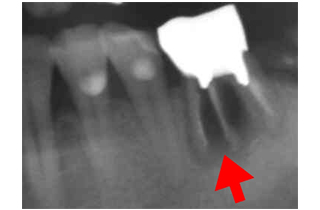

歯科用CTによる立体診断

• 歯や顎の状態を3Dで撮影・診断できる歯科用CTを院内に導入

• むし歯や歯の根、神経の位置などを事前に把握することで安全かつ精密な治療が可能